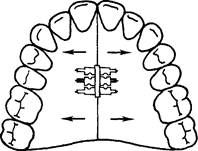

При равномерном сужении левой и правой половины зубного ряда целесообразно применять расширяющую пластинку с расположением винта на уровне срединного небного шва (рис. 13.36). При необходимости перемещения одного зуба или группы зубов в трансверсаль-ном направлении изготавливают пластину с секторальным распилом на верхнюю челюсть (рис. 13.37). При более значительном сужении переднего участка зубного ряда следует использовать расширяющую пластинку с петлей для ограничения расширения боковых участков зубного ряда (рис. 13.38).

Рис. 13.36. Расширяющая пластинка на верхнюю челюсть.